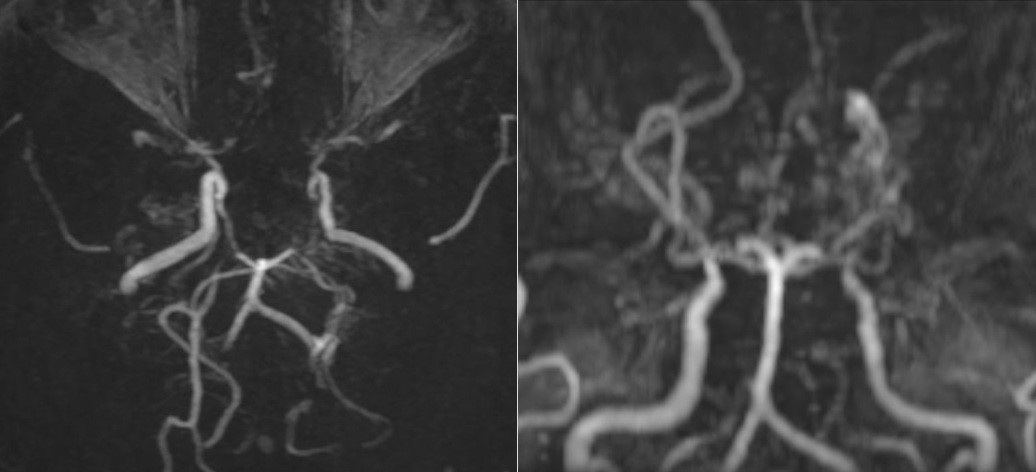

Kết quả chụp cộng hưởng từ (MRI) sọ não khiến bác sĩ khá bất ngờ với tổn thương hẹp, tắc động mạch cảnh trong hai bên và các nhánh của đa giác Willis. Quanh vùng tổn thương, hình thành tuần hoàn bàng hệ với nhiều mạch máu nhỏ bất thường, tạo thành hình ảnh tỏa mờ giống “khói thuốc”.

Ảnh chụp MRI cho thấy mạch máu của bệnh nhân mờ như “khói thuốc”.

Kết quả khám lâm sàng nhận thấy người bệnh không có dấu hiệu thần kinh khu trú hay tăng áp lực nội sọ. Khi chụp cộng hưởng từ (MRI) sọ não, bác sĩ phát hiện hình ảnh tổn thương hẹp tắc động mạch cảnh trong hai bên và các nhánh, xung quanh có nhiều mạch máu nhỏ bất thường. Trên phim chụp mạch não, các mạch này tạo thành đám, tỏa mờ như “làn khói thuốc lá” – dấu hiệu đặc trưng của bệnh Moyamoya.

Các mạch máu não của bệnh nhân nhìn như “làn khói thuốc lá” trên phim chụp MRI. Ảnh: Bệnh viện cung cấp